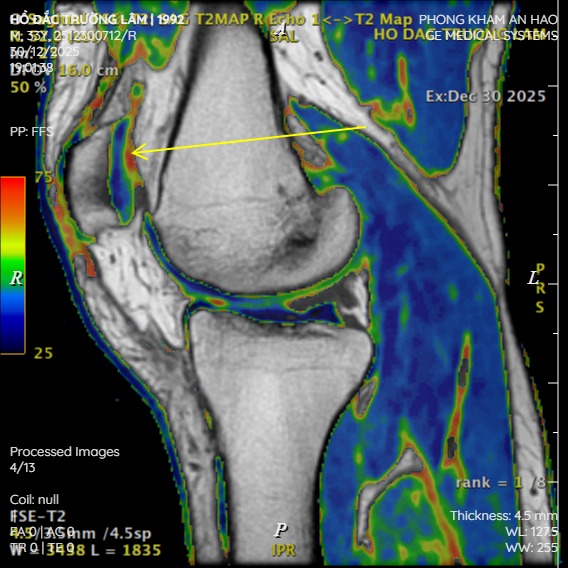

Các kỹ thuật MRI định lượng

| Kỹ thuật MRI | Thông số đo | Ý nghĩa lâm sàng |

|---|---|---|

| T2 Mapping | Thời gian giãn ngang T2 | Phát hiện rối loạn cấu trúc Collagen và tăng nước sớm |

| T1ρ Mapping | Thời gian T1 rho | Nhạy với Proteoglycan – phát hiện thoái hóa sinh học rất sớm |

| dGEMRIC | Chỉ số GAG trực tiếp | Tiêu chuẩn vàng đánh giá Proteoglycan (cần tiêm thuốc cản quang) |

| UTE Imaging | Thời gian echo siêu ngắn | Đánh giá lớp sâu và vùng vôi hóa của sụn |

MRI định lượng có thể phát hiện thoái hóa sụn sớm hơn triệu chứng lâm sàng 3-5 năm, mở ra cơ hội vàng cho điều trị bảo tồn – Khi sụn còn khả năng tái tạo và hồi phục.